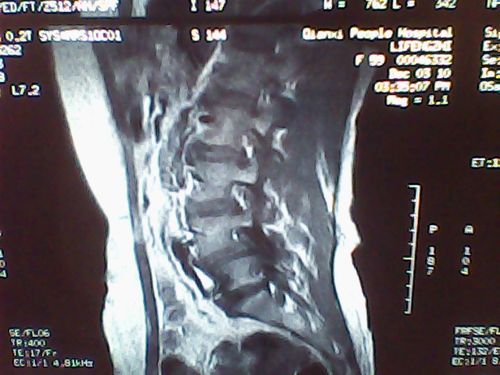

腰椎4一5节滑脱图

腰椎4一5节滑脱图,腰椎滑脱1度图片

快速了解腰椎滑脱

收藏丨腰椎滑脱程度的等级清晰图解

腰椎滑脱症综述附图解

腰椎滑脱图片示意图

腰椎滑脱一二三四度图

腰椎滑脱的图片

腰椎滑脱图片

腰椎滑脱图片怎么看